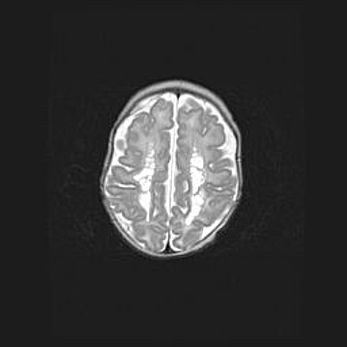

Множественные кисты обоих полушарий головного мозга, наибольшая из них в правой затылочной области. Ассиметричная атрофическая гидроцефалия.

Возраст: 7 месяцев

Вес: 5660 г

Пол: мужской

Окружность головы: 41,5 см

Срок гестации: 28-29 недель

Кисты головного мозга развиваются в результате многоочаговых некрозов вещества мозга и возникают вследствие перенесенной перинатальной инфекции, менингитов, энцефалитов, асфиксии, родовой травмы, расстройств мозгового кровообращения различного генеза. Образованию кист в веществе головного мозга плодов и новорожденных способствуют такие факторы, как высокое содержание в нем воды, недостаточная (или отсутствие) миелинизация и слабая астроглиальная реакция на повреждение.

Кисты могут сочетаться с гидроцефалией и другими поражениями головного мозга.